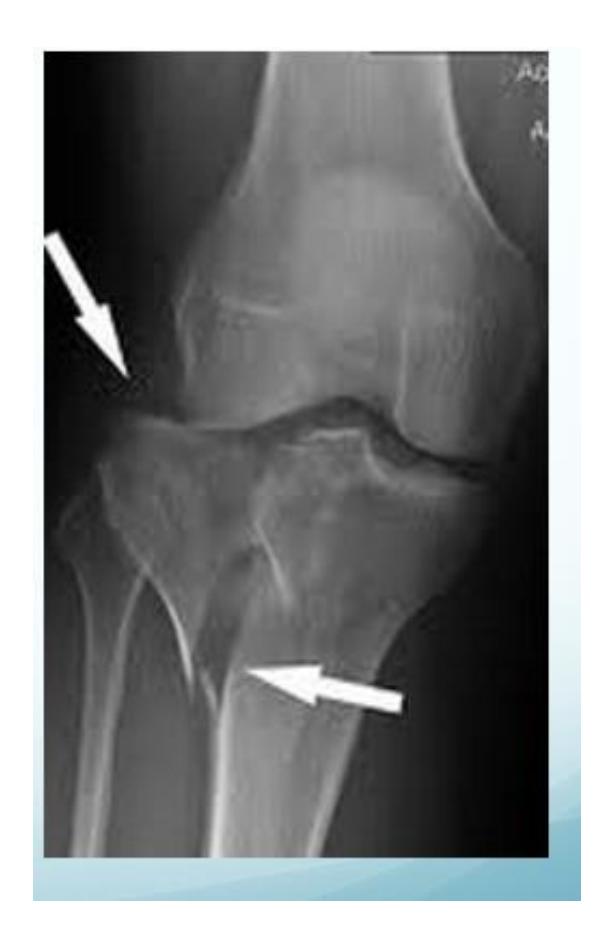

Tibial Plateau Fracture

Diagnosis: Tibial Plateau fracture Characteristics: Intra-articular Treatment: ORIF CT scan is necessary for evaluation